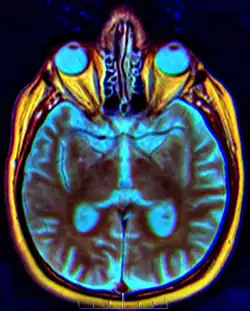

O quiasma óptico é uma estrutura em formato de X formada pelo encontro de dois nervos ópticos. Localiza-se na parte anterior do assoalho do III ventrículo. Recebe as fibras dos nervos ópticos, que ai cruzam em parte e continuam nesse trato que se dirigem aos corpos geniculados laterais. Como resultado temos que cada hemisfério cerebral recebe informações sobre o campo visual contralateral de ambos os olhos. Ver olho.[1]